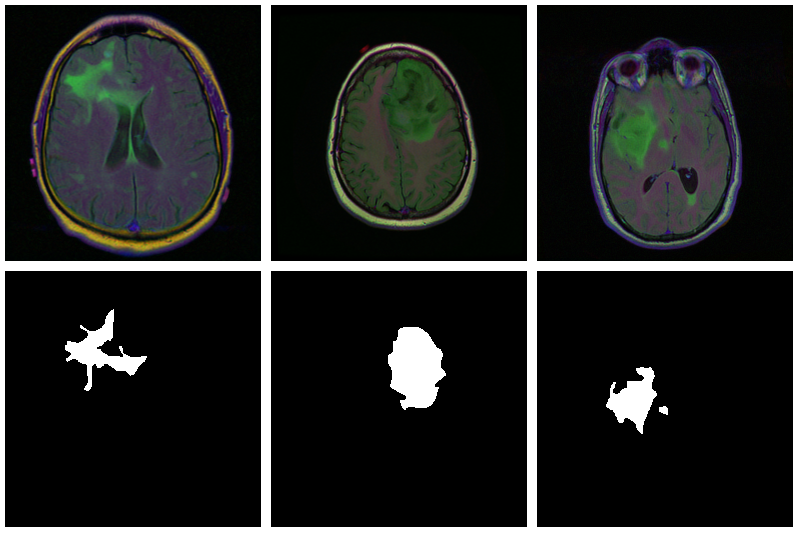

With torch, it is straightforward to inspect what happens when you change augmentation-related parameters. We just pick a pair from the validation set, which has not had any augmentation applied as yet, and call valid_ds$<augmentation_func()> directly. Just for fun, let’s use more “extreme” parameters here than we do in actual training. (Actual training uses the settings from Mateusz’ GitHub repository, which we assume have been carefully chosen for optimal performance.1)